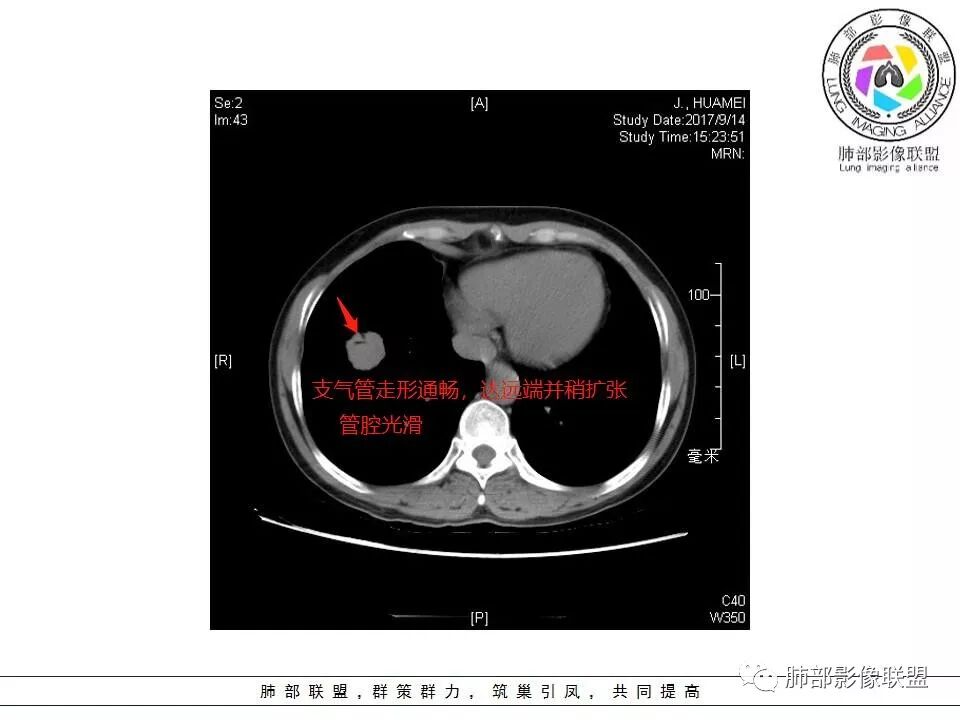

内部支气管扩张,穿行血管形态自然,支持malt。

右肺下叶前基底段结节 边缘磨玻璃密度较清 内部支气管扩张,轻中度强化 穿行血管形态自然,支持淋巴瘤。

边缘彭隆,还是考虑肿瘤,支气管通入,肺内原发,支气管自然穿行稍扩张,血管比较自然同行,漂浮征,增强后整个比较均匀无明显坏死,淋巴瘤首选。恶性应该没有问题,建议穿刺。

内部支气管走形非常自然,达远端稍扩张;内部血管穿行也非常自然

支气管充气征伴或不伴支气管扩张:肿瘤细胞沿肺间质及支气管黏膜下组织浸润,支气管管壁未见明显破坏,管腔内未见肿瘤细胞充填,呈现充气支气管征;充气支气管走行自然,无扭曲、僵硬,内壁管腔光滑,支气管管壁见增厚并常有管腔的扩张,含气支气管可呈串珠样不均匀扩张,扩张明显处呈空腔样或皂泡样的囊状含气影;支气管扩张目前有两种意见:一是由于肿瘤组织起源于肺间质,肿瘤沿或跨越脏器解剖结构生长,原有解剖结构残留,周围增生的纤维结缔组织牵拉导致支气管扩张;二肿瘤侵犯支气管粘膜下植物神经丛致平滑肌张力丧失;而这类支气管扩张在肿瘤治疗后有时可消失。